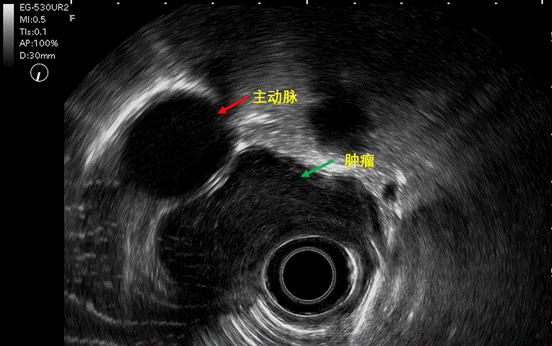

超声内镜是内镜中的望远镜,既有内镜检查的直观性,又有超声检查的穿透性,可以穿透肠壁看到远处,结果显示,可能是平滑肌瘤。随后的CT检查也显示,大概率是良性。

这个肿物虽然是良性,但很大,长10公分,占据整个食管的三分之一,宽5公分,跨食管壁生长,几乎堵塞食管腔,部分长在腔外,紧邻胸主动脉、主动脉弓和支气管分叉,特别是和主动脉之间只有毫米之隔,术中万一损伤主动脉,分分钟下不了台。